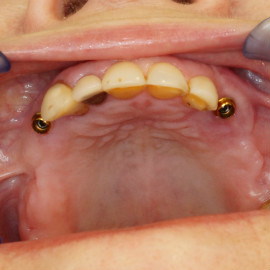

• Implanty jako zakotwiczenie protezy częściowej i całkowitej

Nie u każdego pacjenta można wykonać stałe odbudowy protetyczne oparte na implantach. Powody najczęściej sa prozaiczne, takie jak koszty, niekorzystne początkowe warunki kostne i wymagane rozległe odbudowy kości, strach przed bólem a także - jakże często - zdrowy rozsądek. Wiadomo bowiem, że w przypadku rozległych, trudnych technicznie do wykonania regeneracji kostnych zwiększa się obciążenie organizmu, oraz możliwości wystąpienia powikłań, a więc zwiększa się ryzyko niepowodzenia w leczeniu. Dlatego wykorzystujemy implanty jako zakotwiczenie atachmentów do utrzymania protezy ruchomej. Takie rozwiązanie pozwala na zmniejszenie kosztów, ograniczenie zakresu zabiegu, oraz co najważniejsze pozwala na poprawę jakości życia i zadowolenia z użytkowania protez ruchomych.

Pacjentka głosiła sie do naszego gabinetu do leczenia z osadzonym mikroimplantem w pozycji lewej dolnej dwójki. Siostrzany implant w pozycji prawej dolnej dwójki wypadł wcześniej, około 1,5 roku od implantacji. Odtworzono przedsionek i dziąsło rogowaciejące, osadzono dwa implanty, jednoczasowo z regeneracją kości. Dopiero na etapie ostatecznej rekonstrukcji protetycznej usunięto zachowany mikroimplant. To się nazywa motywacja do leczenia! Pacjentka przygotowywała sie na ślub prawnuczki :)